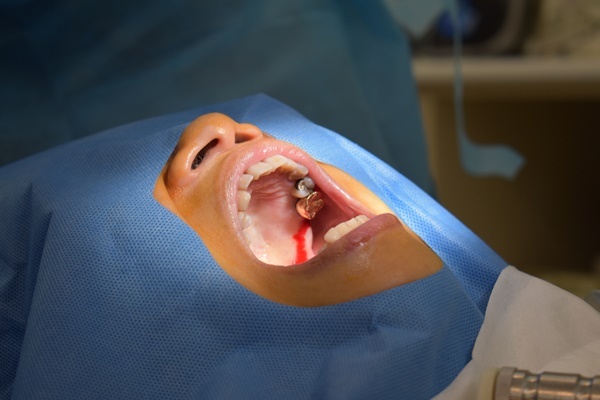

一旁有個護士不停拿著吸水管在她嘴巴裡面游移吸走那些口水,為了要陪她做手術護士也請我換上跟醫師一樣的藍色手術衣跟帽子,都感覺自己變成植牙醫師一樣要幫她做手術,然後就看著護士幫她蓋上一塊綠色洞巾只露出嘴巴,劉有恆醫師動作很快地在牙齒位置四周圍又補了近六隻的麻醉藥。

動作很迅速拿著檯面上器械搬弄她的嘴唇執行著微創植牙,瞬間看到血淋淋畫面上演著,鑽開牙肉後些微的血絲,醫生還逗趣對著我說要我瞪大眼睛看一下,等下就可以看到薄薄的灰白色就是骨頭,接著拿起鑽子在骨頭上打洞鎖上很小的螺絲釘(貌似俗稱的植牙專用植體)

螺絲釘打好之後劉醫師就跟一旁護士說拿骨粉過來,用很細的鑷子拿起兩塊白色物狀塞到翻開的牙肉裡面,再使用像剪刀彎鉤的器械做傷口縫合,看到劉醫師這樣縫補傷口當下我心裡想這位醫師應該在家應該是負責縫補衣服吧!!手工了得~~~

微創植牙果然如傳說中快速還沒有十分鐘劉醫師就完成治療,護士接著拿著酒精棉布幫我媽把嘴巴四周圍藥水很用心擦拭過一遍,再拿微創植牙手術保養單仔細叮嚀我帶媽媽回家後要怎麼幫她做傷口保養,手術後48小時內臉部會紅腫冰敷盡量不要停….等等,離院前護士準備一個很可愛的牙齒冰敷袋&植牙漱口水可以帶回家,這次目睹我媽最微創植牙並沒有想像中來得恐怖,和拔智齒比較起來好像植牙容易簡單多啦!!